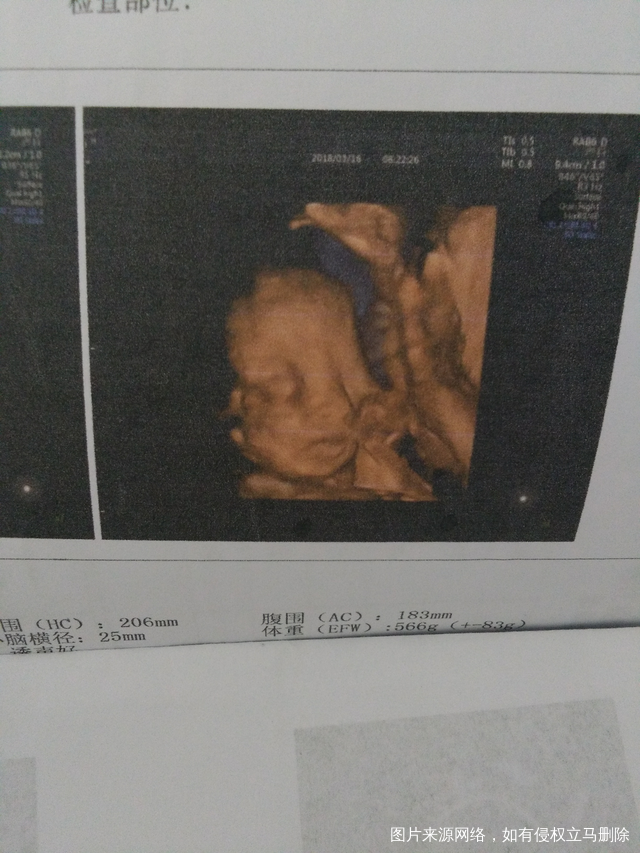

说看到四维彩超照片好丑,我觉得都挺好看的嘛,大家看看我家宝宝四维彩超丑嘛?